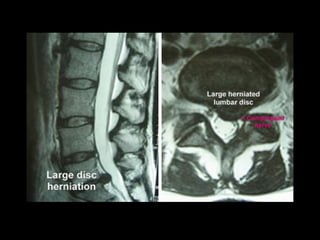

Disc Herniation

Diagnostic Findings

Disc Herniation • Inthe lumbar spine, at least 90% of disc herniations occur at the L5–S1 or L4–5 levels. L3–4 herniations make up only 5% of cases, with the remainder occurring at L2–3 and L1–2 • Clinically, a herniated disc at one level usually affects the nerve root that exits at the level below. For instance, a left L4–5 disc herniation usually compresses the left L5 nerve root

Disc Herniation Signs &SX • Initial complaints are backache, and in most of those affected, there is no history of antecedent trauma • Prior similar complaints of back pain or sciatica are common complaints • The patient 's back pain is usually followed by severe pain that radiates into the lower extremities • Numbness or paresthesias may occur in the same distribution as the pain, and weakness of selected muscle groups can occur